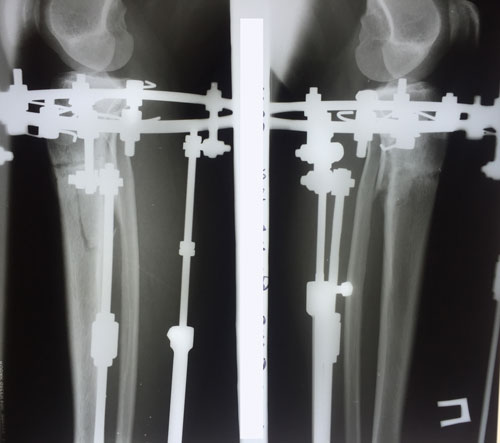

рентген в 90 дней.

Здравствуйте, Iskorka! По рентгену, сращение отличное, ждём на снятие аппаратов.